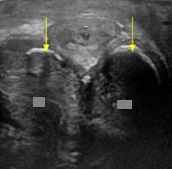

Identify this image.

Peripheral zone

Central and transitional zone

Urethra